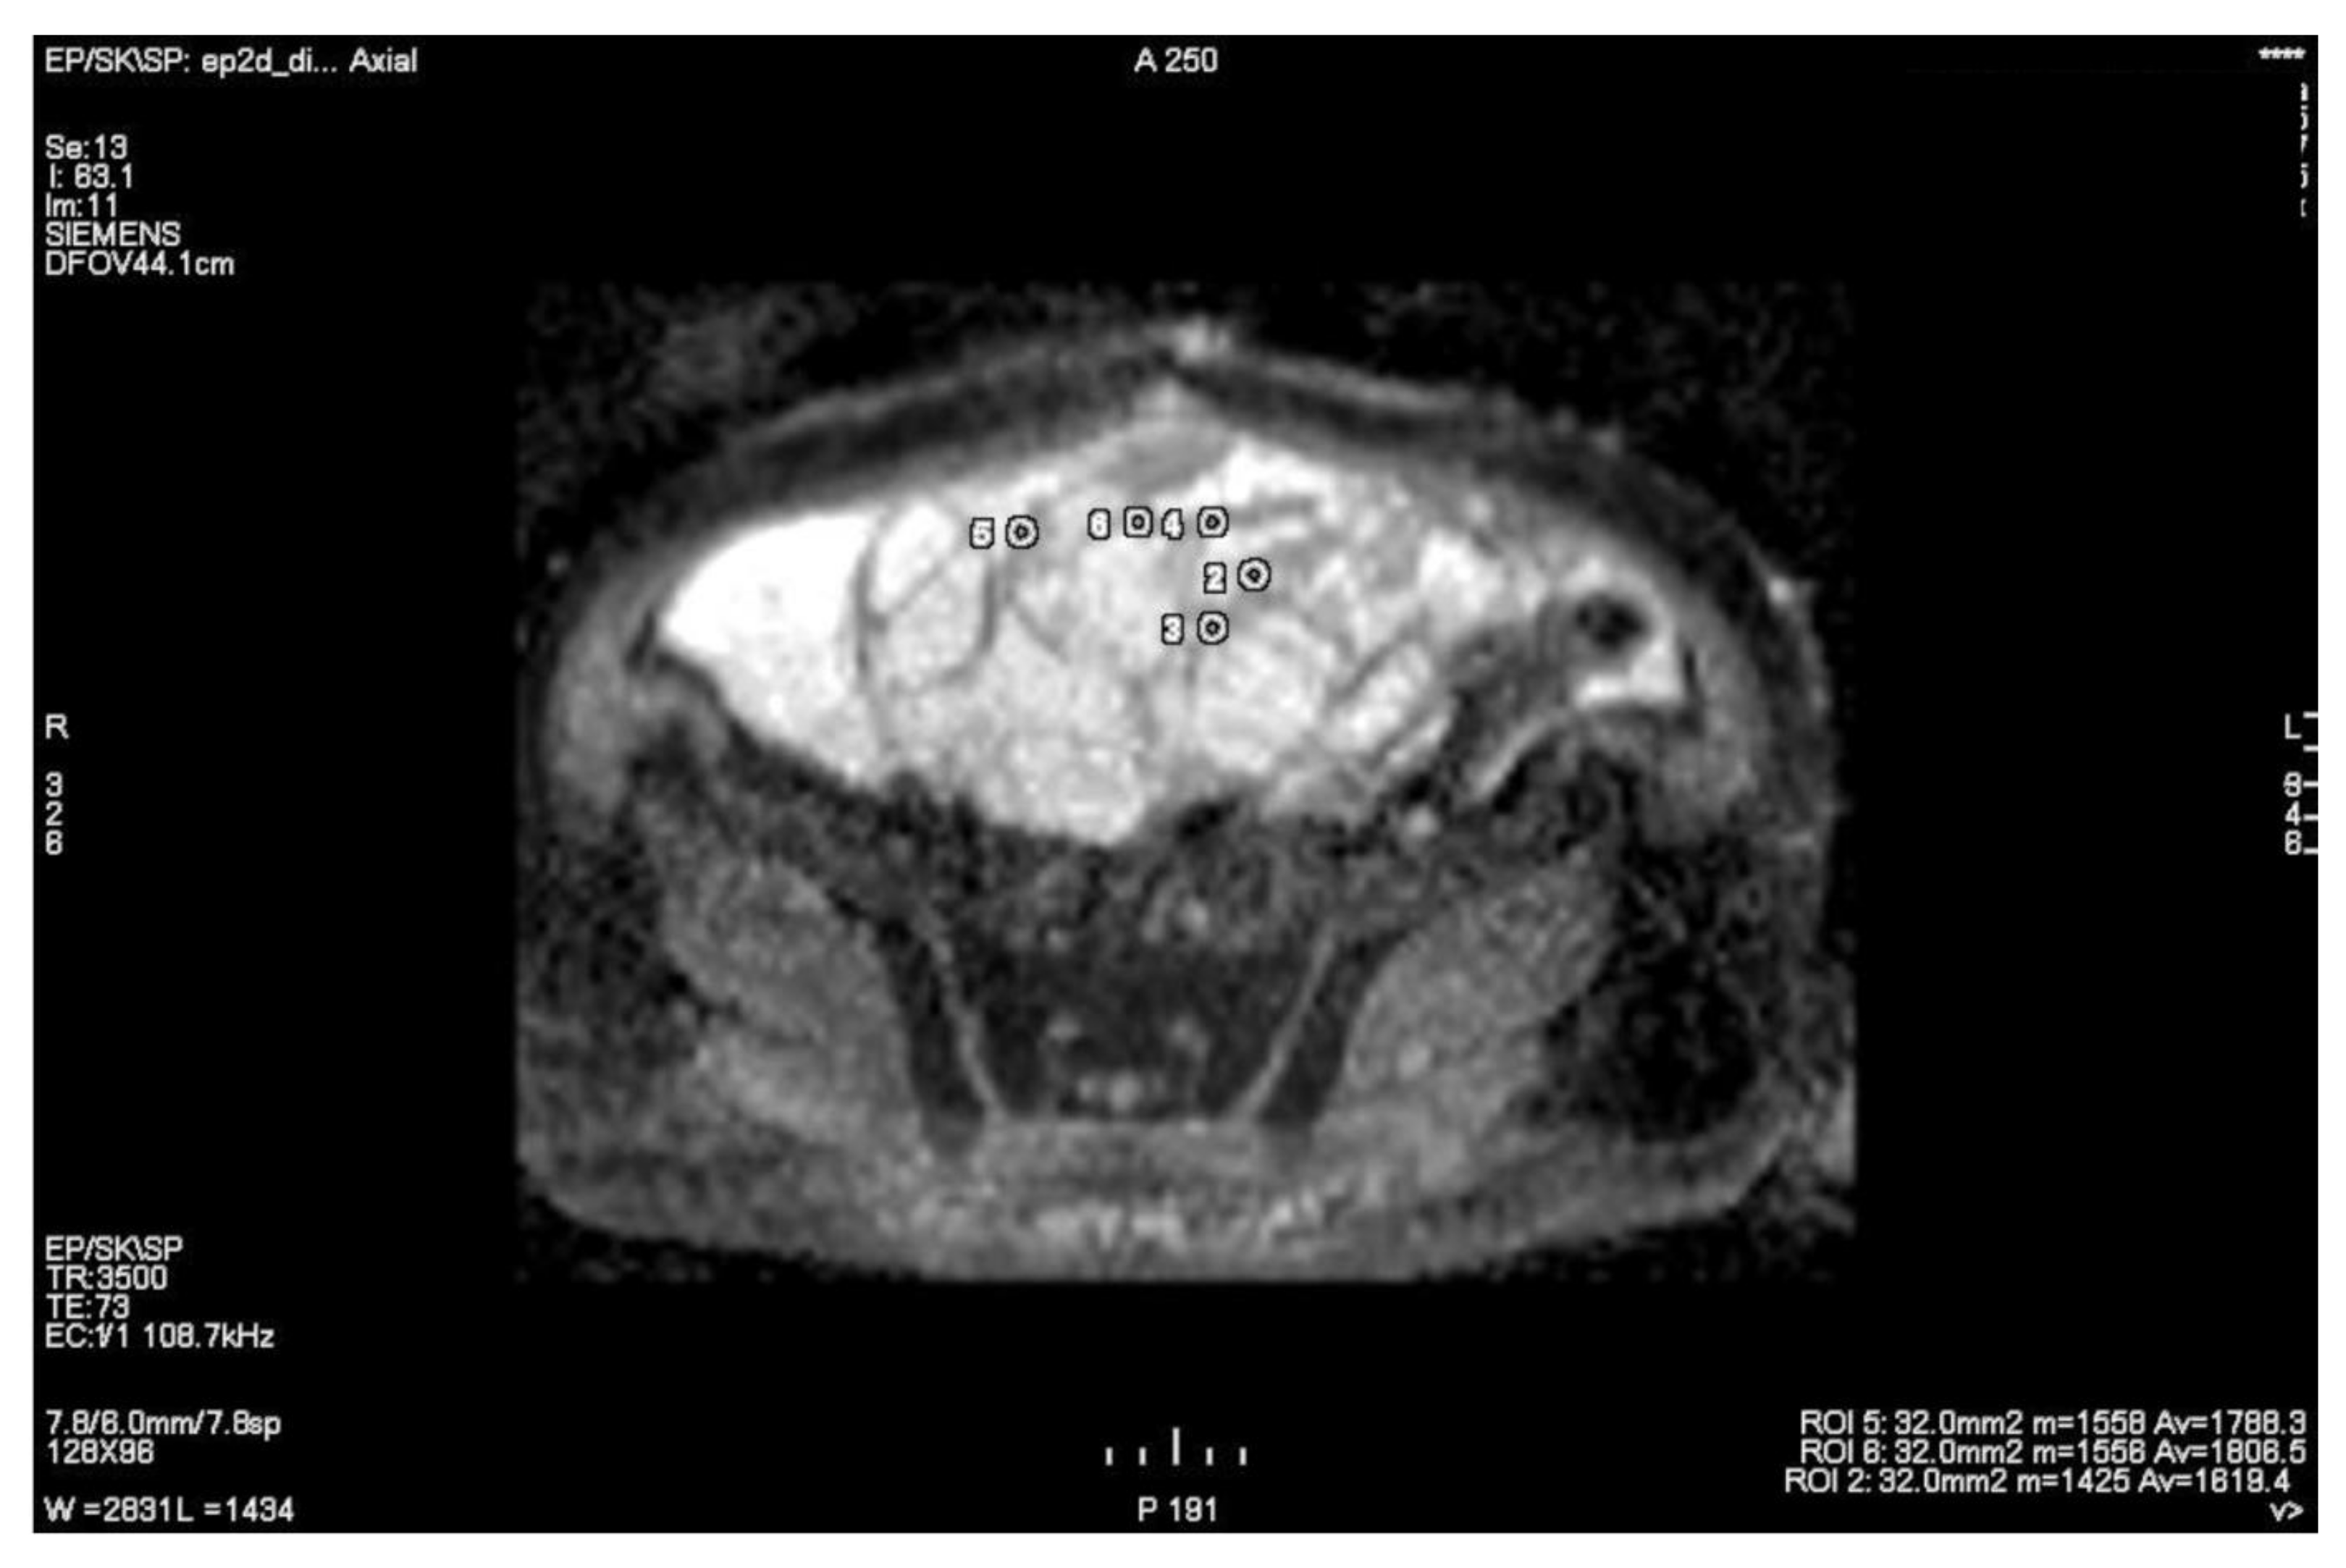

3.1. Primary Tumor DWI

3.2. Inter-Observer Agreement